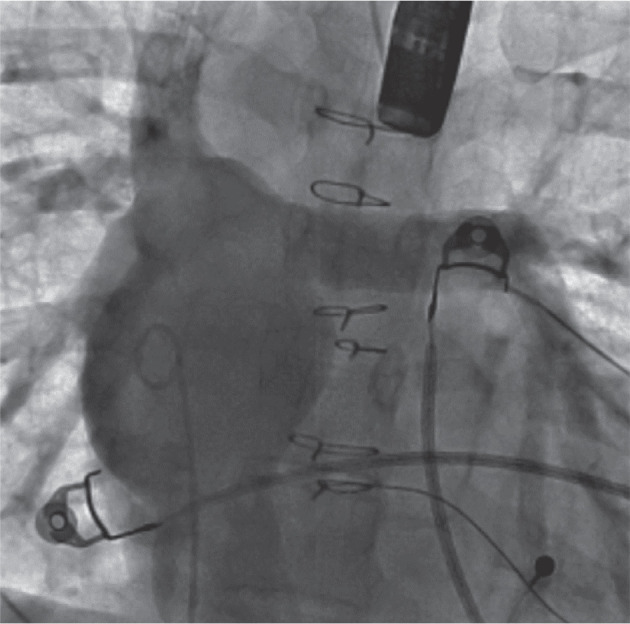

Current leadless pacemaker (LP) systems, which have been developed and used in patients with normal cardiac anatomy, are rare and technically even more challenging to implant in patients with congenital heart diseases, especially with univentricular physiology and Fontan palliation. We report two cases of percutaneous LP implantation in an adult and a child, respectively, highlighting the unconventional approaches, different challenges, and use of multimodality imaging in patients who underwent a Fontan operation.